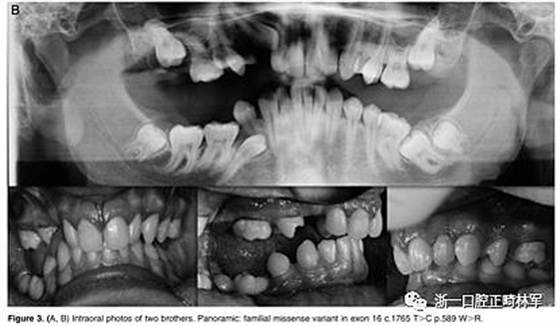

最后,在数据库中以前没有报道的错义变体在外显子16 c.1765 T>C p.Trp89Arg中发现。 在同一家庭的三个成员 - 母亲,女儿和儿子(图3A,B)中发现的错义变体-负责用精氨酸p:Trp89Arg取代氨基酸色氨酸,这是一种具有不同化学特性的氨基酸。该突变发生在PTH1R蛋白质的胞质结构域中,并参与受体与激活细胞内级联信号的G蛋白的相互作用。此外,计算机结果表明,PTH1R蛋白质中的这种氨基酸取代改变了蛋白质的结构和功能,因为它发生在蛋白质的催化结构域内。

图3.(A,B)两兄弟的口内照片。全景:外显子16中的家族错义变体c.1765 T>C p.589 W>R

属于2号家庭的小女儿(2:2)表现出更复杂的临床表现,缺乏永久性以及暂时性系列和囊性结构元素的萌出(图3A,B)。在哥哥(II:1;图3A,B)中发现由于包括多颗恒牙的严重的双侧后牙开合。最后,患者II:1和II:2的母亲表现出双侧上颌第一磨牙和下磨牙的包埋。发现前磨牙层面没有咬合接触(图3A,B)。